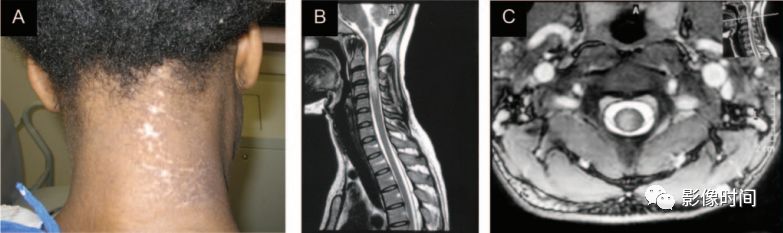

带状疱疹脊髓炎:患者往往存在带状疱疹病史

MRI:

发病皮区相对应的单侧脊髓节段受累,T2WI 为高信号

发病皮区相对应脊髓层面出现T2WI高信号